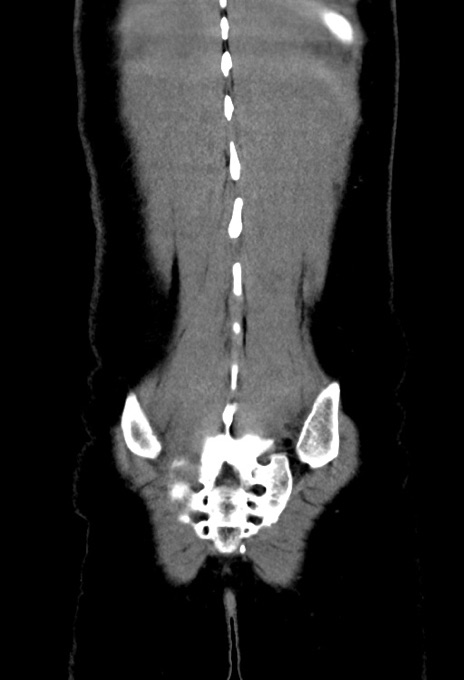

症例17(冠状断像)

横断像

【症例】20歳代女性

【主訴】嘔吐、下腹部痛

【現病歴】昨日夕食後に嘔吐し下腹部痛が出現。本日になっても嘔吐持続し改善しないため来院。

【身体所見】意識清明、BT 37.2℃、BP 108/67mmHg、腹部:平坦、やや硬、下腹部正中から右にかけて圧痛あり、反跳痛軽度あり、tapping pain(+)。

【データ】WBC 13600、CRP 14.94